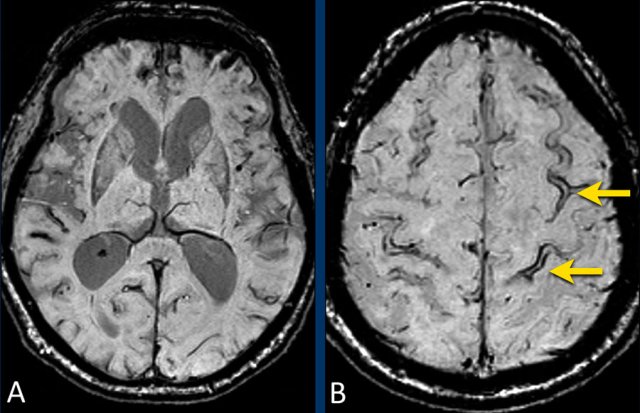

Cortical superficial siderosis in CAA

CAA-related bleeds include:

• Macrobleeds - symptomatic lobar hemorrhages

• Microbleeds - small and typically silent peripherally located

• Cortical superficial siderosis (cSS) - cortical subarachnoid hemorrhages that follow the curvilinear shape of the surrounding cerebral gyri

In superficial siderosis the proximity to the cortical surface appears to be the trigger for transient focal neurologic symptoms or amyloid spells.

CAA patients with widespread cortical superficial siderosis  have a far greater chance for recurrent hemorrhage compared to patients without cSS (ref).

Lobar hemorrhage in Cerebral Amyloid angiopathy (CAA)

This patient with CAA presented with a large lobar hematoma in the right temporal lobe.

Notice the superficial siderosis (arrow).

This patient with CAA has microbleeds, superficial siderosis and multiple infarcts.

Notice the hemorrhage in the pons (yellow arrow).

There is superficial siderosis in the left occipital region.